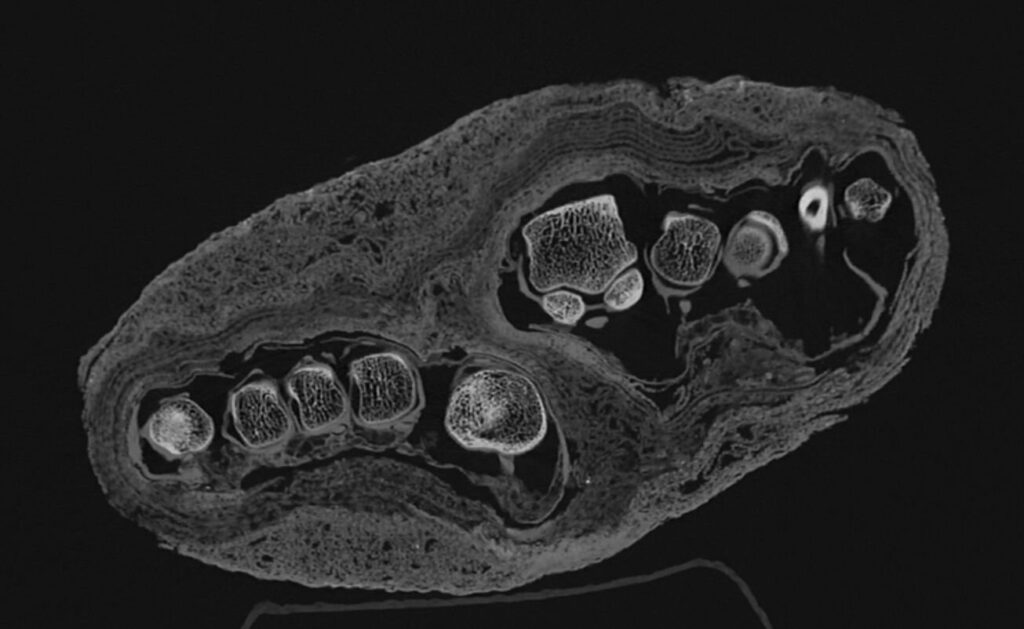

这项新成像项目最引人注目的方面之一是能够纠正长期存在的历史误认。在考古学的世界里,事情并不总是表面看起来的那样。其中一组遗骸被送入博物馆,仅被认定为“木乃伊包裹”。由于没有内部成像,最初被归类为人头。后来,有人推测它可能是鸟的木乃伊。

直到CT技术的帮助,真相才浮出水面:包裹里实际上是一只木乃伊化的成年脚。新的高分辨率扫描现在更进一步,分析包裹在肢体上的绷带的不同层次。图像清晰显示纺织残片中不同的结构特征,可能为具体木乃伊制作技术及个体是否患有任何可识别疾病提供线索。虽然研究人员认为这只脚最初是完整木乃伊的一部分,但它被分离的原因以及解剖的时间仍然是团队仍在努力解开的谜团。